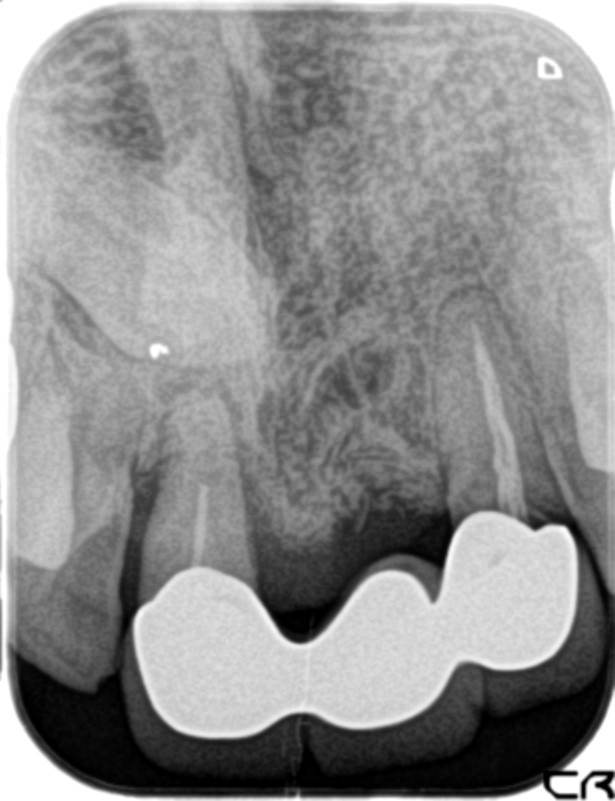

症例140代 男性 主訴 奥歯に歯を入れたい、しっかり噛みたい

治療前

治療後(5年経過)

主訴 奥歯がない為、食事が不自由である。入れ歯は煩わしいので、固定制のインプラントにして欲しいと訴え来院。口腔内全体で6本のインプラントを埋入。仮歯にて神経筋機構、顎関節のバランスを整え、リハビリを経て、約5ヶ月後にジルコニアを装着。

リスクとしては、外科的侵襲がある。デメリットは、保険外診療の為、経済的負担がある。

費用 316万(税込) (オペ・仮歯・最終補綴物まで含む)